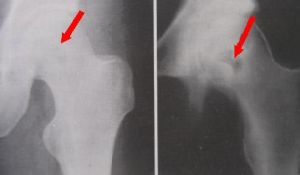

腿部膿液培養

形態染色革蘭陰性短小桿菌、無芽孢、無莢膜,菌體兩端鈍圓並深染,中心著色較淡。

培養特性膿液標本接種於血平板,37℃、24h培養形成0.6~1.1mm淡紫色菌落,略凸,光滑,呈擴散狀,有甲型溶血環,普通培養基上菌落呈明顯的紫色,中等大小。麥康凱瓊脂培養基上生長良好,菌落呈紫黑色,半固體,培養基有動力,表面與空氣接觸處呈紫色。克氏雙糖鐵培養基底層產酸,斜面產鹼,有紫紅色菌落生長,不產生H2S和氣體。營養肉湯,混濁生長,液面有淡紫色菌膜,pH8.5,腖水混濁生長,不產色素。

生化特徵分解葡萄糖、果糖,產酸不產氣,不分解麥芽糖、木糖、蔗糖、阿拉伯糖、棉子糖、甘露醇、苯丙氨酸、葡萄糖酸鹽、靛基質、甲基紅、V-P、尿素酶、鳥氨酸、DNA酶均陰性,精氨酸為陽性。氧化酶、觸酶陰性,硝酸鹽還原。明膠遲緩液化。O-F∶F。

本菌一般為條件致病菌,臨床較為罕見。我們從膿液中分離出來,根據以上特徵鑑定為紫色色桿菌。根據藥敏實驗進行抗感染治療,病情日漸好轉。